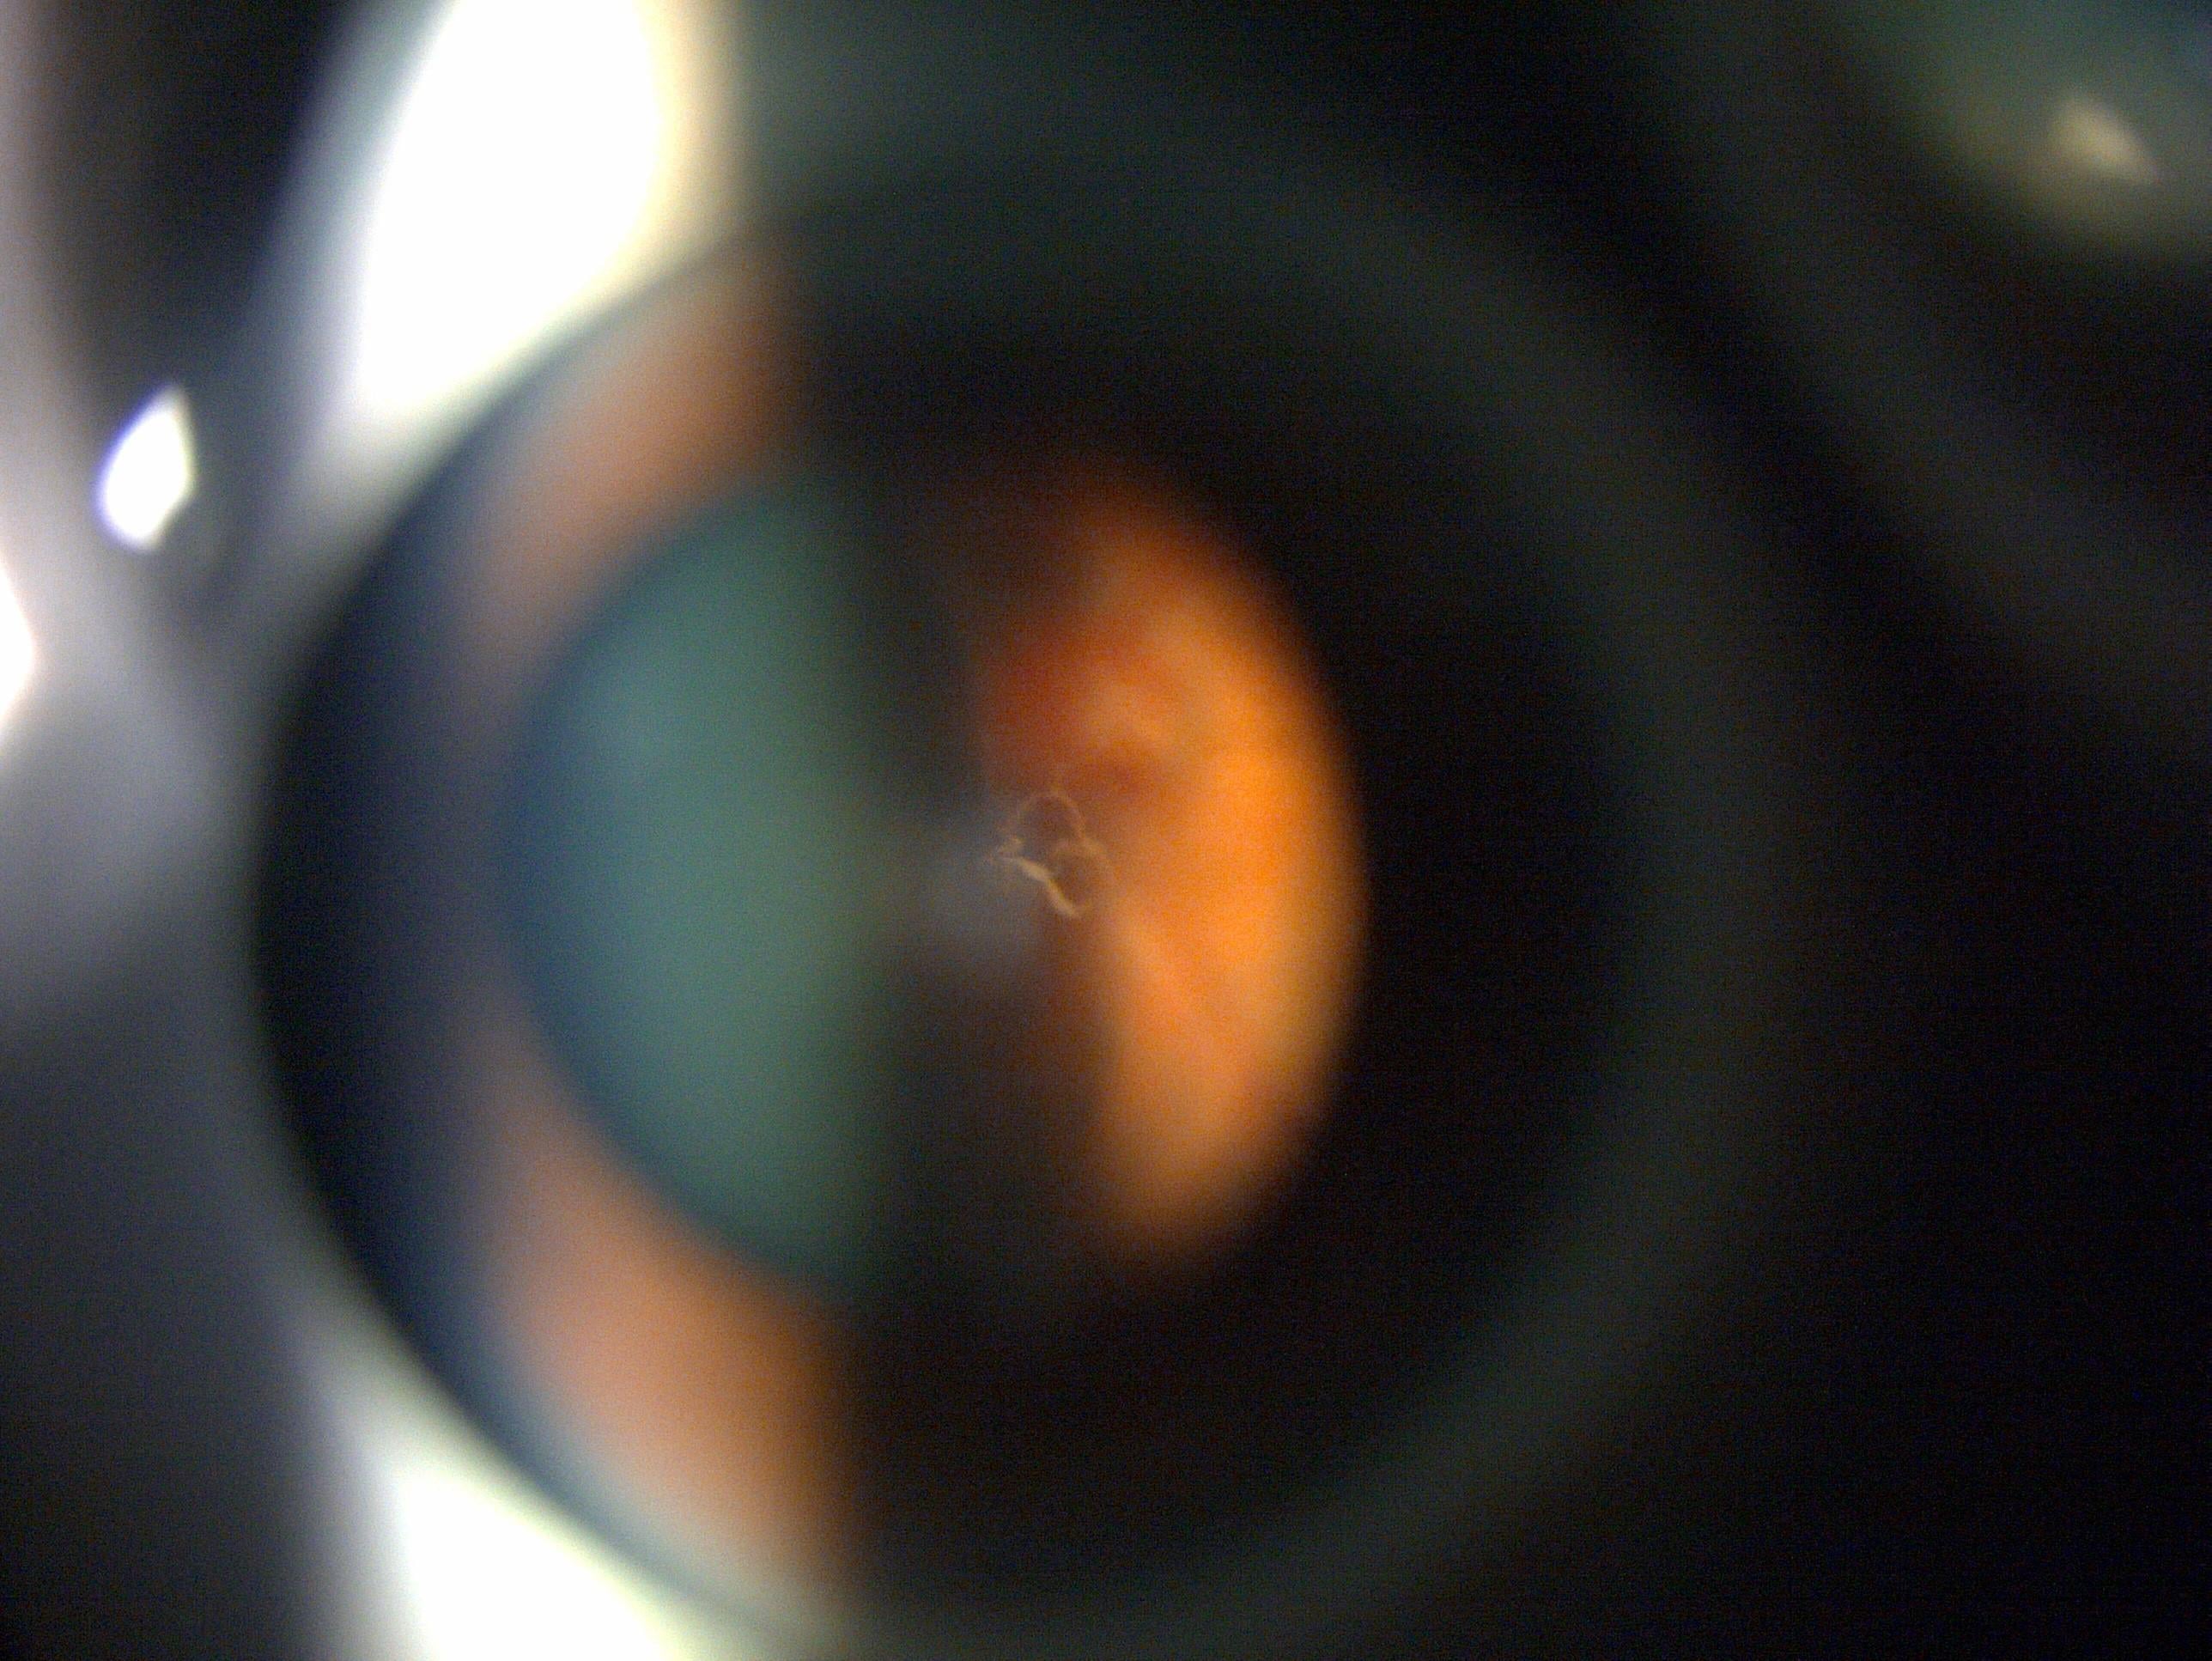

我們視物就像目光透過一個金魚缸,如果水變得混濁,就會看到有半透明東西在眼前飄浮,這就是飛蚊症了。當玻璃體老化時會變得混濁,便會出現飛蚊症狀,若因玻璃體老化萎縮而撕扯到視網膜,視線就會出現閃光,像有人在用閃光燈拍照一般。如果視網膜因此而破洞,飛蚊症狀會急劇增加,也會出現閃光視覺,一旦有這些狀況發生,就要盡快求醫做眼科檢查,若然置之不理視網膜可能會完全脫落,導致視力驟降,或周邊視野有黑影,彷似戲院落幕一樣,嚴重甚至眼前有大片黑影,造成不可逆轉的視力缺失或失明。

如果只是玻璃體老化,與視網膜分離是毋須手術治療的,只需持續觀察視網膜有沒有破損情況,即使有飛蚊症狀亦屬正常。若不幸發現視網膜破洞,就要進行激光治療修補。病情惡化至視網膜剝落的話,治療手術會更複雜,若液體流到黃斑點,部分視力損傷即使手術也不能逆轉,所以盡早求醫非常重要。